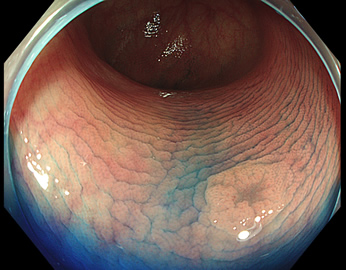

TXIは、「画像の構造を強調する」技術です。これは特別に目新しいものではありません。パソコンの画像編集ソフトや、スマホのアプリでも御馴染みの技術です。しかし、「どのような構造強調が実際に、内視鏡に一番、合うか?(強すぎると不自然になる!)」は、難しい(アナログ的な)課題です。オリンパス社は数タイプのTXIモードを用意しました。半年間の試行錯誤の末、今では下記のモードがベストと判断しました。そして今では「TXI無しの内視鏡は不要(フルタイムTXI)」というまで常用しています。

以下に実例を挙げます

写真だけ、見ると「言われてみるとTXIの方が認識しやすい。でも僅かの差」と感じるでしょうが、この「僅かの差」が、人間の脳での検出には大きな差になります。青い色素(インジゴ・カルミン)が非常に強調され、粘膜の凸凹が明瞭になるのが特徴です。

通常観察 TXIモード

青い色素は追加していません![]()